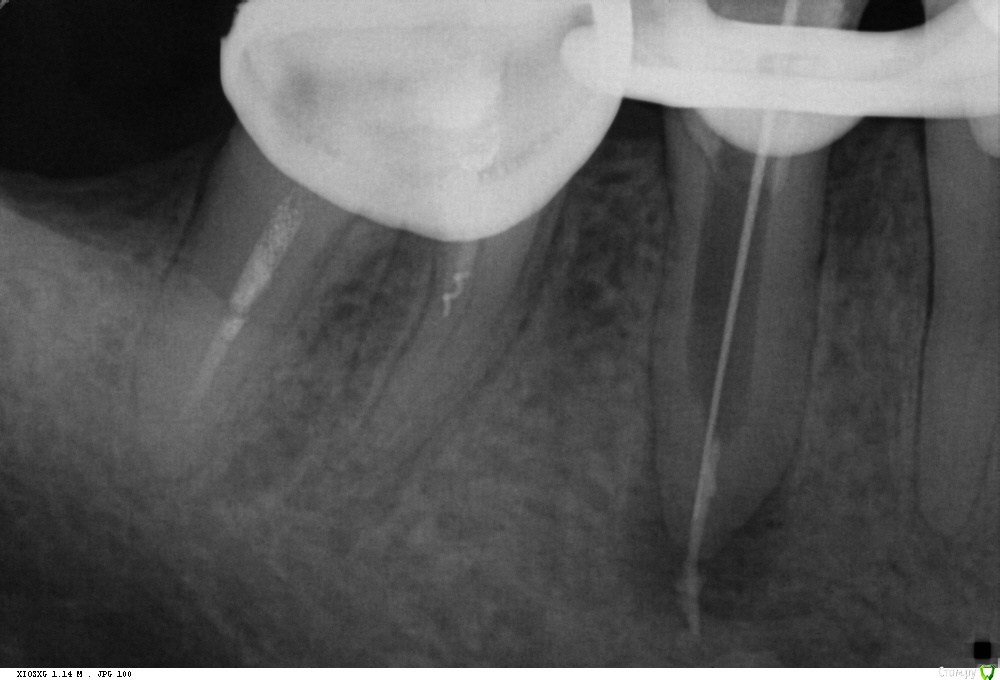

St. Опубликовано 13 октября, 2016 Поделиться Опубликовано 13 октября, 2016 История такова. Год назад зуб был с большой пломбой, но без периапикальных изменений на панораме. Никак себя не проявлял. 2-3 мес.назад со слов стал ныть, потом боль стала сильнее и проходила только от холодной воды. Тут вроде как ясно, классический гнойный пульпит. Болел ли тогда при накусывании пациент не помнит. Пошел к врачу, за 1 прием полечили каналы. На след.раз поставили постоянную пломбу. Через несколько дней пломба выпала. Поставили новую на стекловолокне. Боль вроде прошла.Сейчас появились боли при накусывании. Учитывая что до этого лечение было в гос и как минимум без коффа, решила перебрать. Не знаю, правильно ли?Но уже как есть. Достала СВЩ не очень удачно - истончила дист. стенку. Распломбировала. То что за апексом - скорее всего силлер( н-файлом не удится ничего). Получили экссудат. Сейчас на гидроокиси. У кого какие мысли как быть дальше? Собственно как лучше запломбировать и чем восстановить зуб после. Ссылка на комментарий

St. Опубликовано 13 октября, 2016 Автор Поделиться Опубликовано 13 октября, 2016 Здорово! Вы молодец!Для меня стекловолокно всегда испытание в каком-то смысле, ненавижу его доставать((Тут тоже ничерта не видно было. Еще и эндочак загнулся как на зло. А результат работы бором на 14 мм вы видите. Крайне неудачно получилось.. Стыдно Ссылка на комментарий